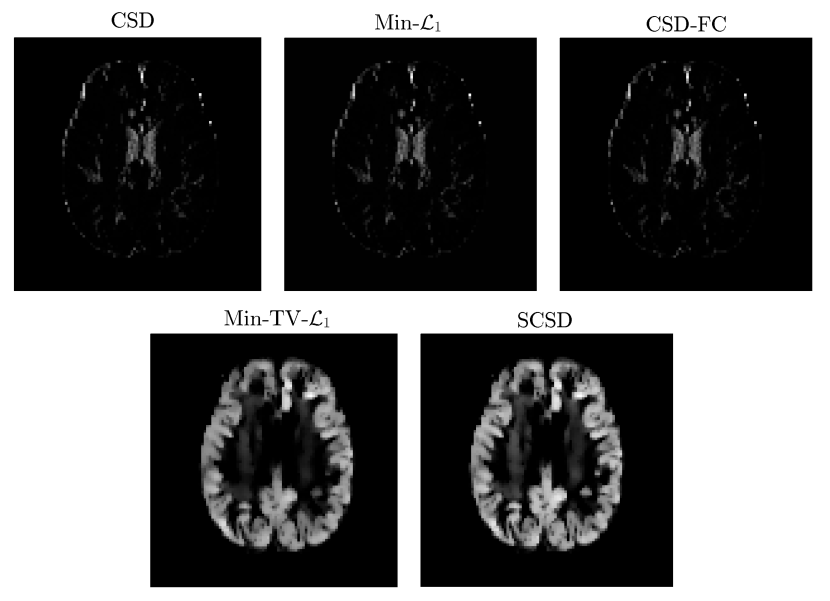

The results of our final quantitative comparison are summarized in Fig. 7, which shows the values of contrast obtained using different SD methods under comparison for s/mm2 (left column of subplots) and s/mm2 (right column of subplots). Predictably enough, the best contrast is achieved by the Min-TV- and SCSD algorithms, owing to their inherent ability to account for the presence of isotropic diffusion. Moreover, out of the two, the proposed SCSD algorithm yields the higher values of for all simulated scenarios. An additional illustration of the effect of incorporation and spatial regularization of the isotropic diffusion component is provided in Fig. 8, which depicts a 2-D “axial” slice of the IDMs reconstructed by different SD methods under comparison for s/mm2, , and . (Note that, for the sake of the clarity of visualization, the IDMs in Fig. 8 have been normalized so as to make their minimum and maximum values correspond to black and white pixel values, respectively.) One can see that the IDM reconstruction produced by SCSD is virtually indistinguishable from the original IDM (as shown in the upper, leftmost subplot of the figure), with the second best result produced by the Min-TV- algorithm. At the same time, neither CSD, Min- nor CSD-FC can attain a comparable accuracy of estimation of the spatial pattern of isotropic diffusion, as represented by the original IDM. In particular, even though their respective reconstructions do bear some global resemblance to the original IDM, the level of estimation errors is too high to deem these reconstructions useful.

Fig. 10 depicts the reconstructions of fODFs obtained using the CSD (Subplot A), Min- (Subplot B), CSD-FC (Subplot C), dRL (Subplot D), Min-TV- (Subplot E), and SCSD (Subplot F) for the axial view and s/mm2. As opposed to Subplots A3-4 and B3-4 in Fig. 9, the fODFs in Fig. 10 are shown superimposed over the values of their corresponding IDMs. Analysing these results reveals the principal drawback of SD methods which disregard the effect of isotropic diffusion. In particular, not only CSD and Min- but also CSD-FC tend to yield spurious estimates of fODFs in anatomical regions corresponding to the cortical grey matter – the result which stands at odds with the fact that these regions are known to be devoid of neural fibre bundles. Further, although being capable of coping with the presence of isotropic diffusion, the dRL algorithm is “blending” and , which effectively impairs the angular resolution, and therefore the resolvability of crossing fibre tracts. Moreover, neither of the aforementioned methods has been found to be capable of reliably recovering the IDMs. At the same time, both Min-TV- and SCSD yield anatomically consistent reconstructions of the IDMs, with much less noisy results obtained in the case of SCSD. (This point is further illustrated by Fig. 11 which shows the “zoomed-out” IDMs recovered by the SD methods under comparison for the case of s/mm2.) Moreover, a closer inspection of Fig. 10 reveals that the fODFs estimated by means of SCSD are characterized by a smoother and more consistent spatial variability (owing to the fibre continuity constraint), thereby exhibiting a better adherence to the expected connectivity within an in vivo brain.